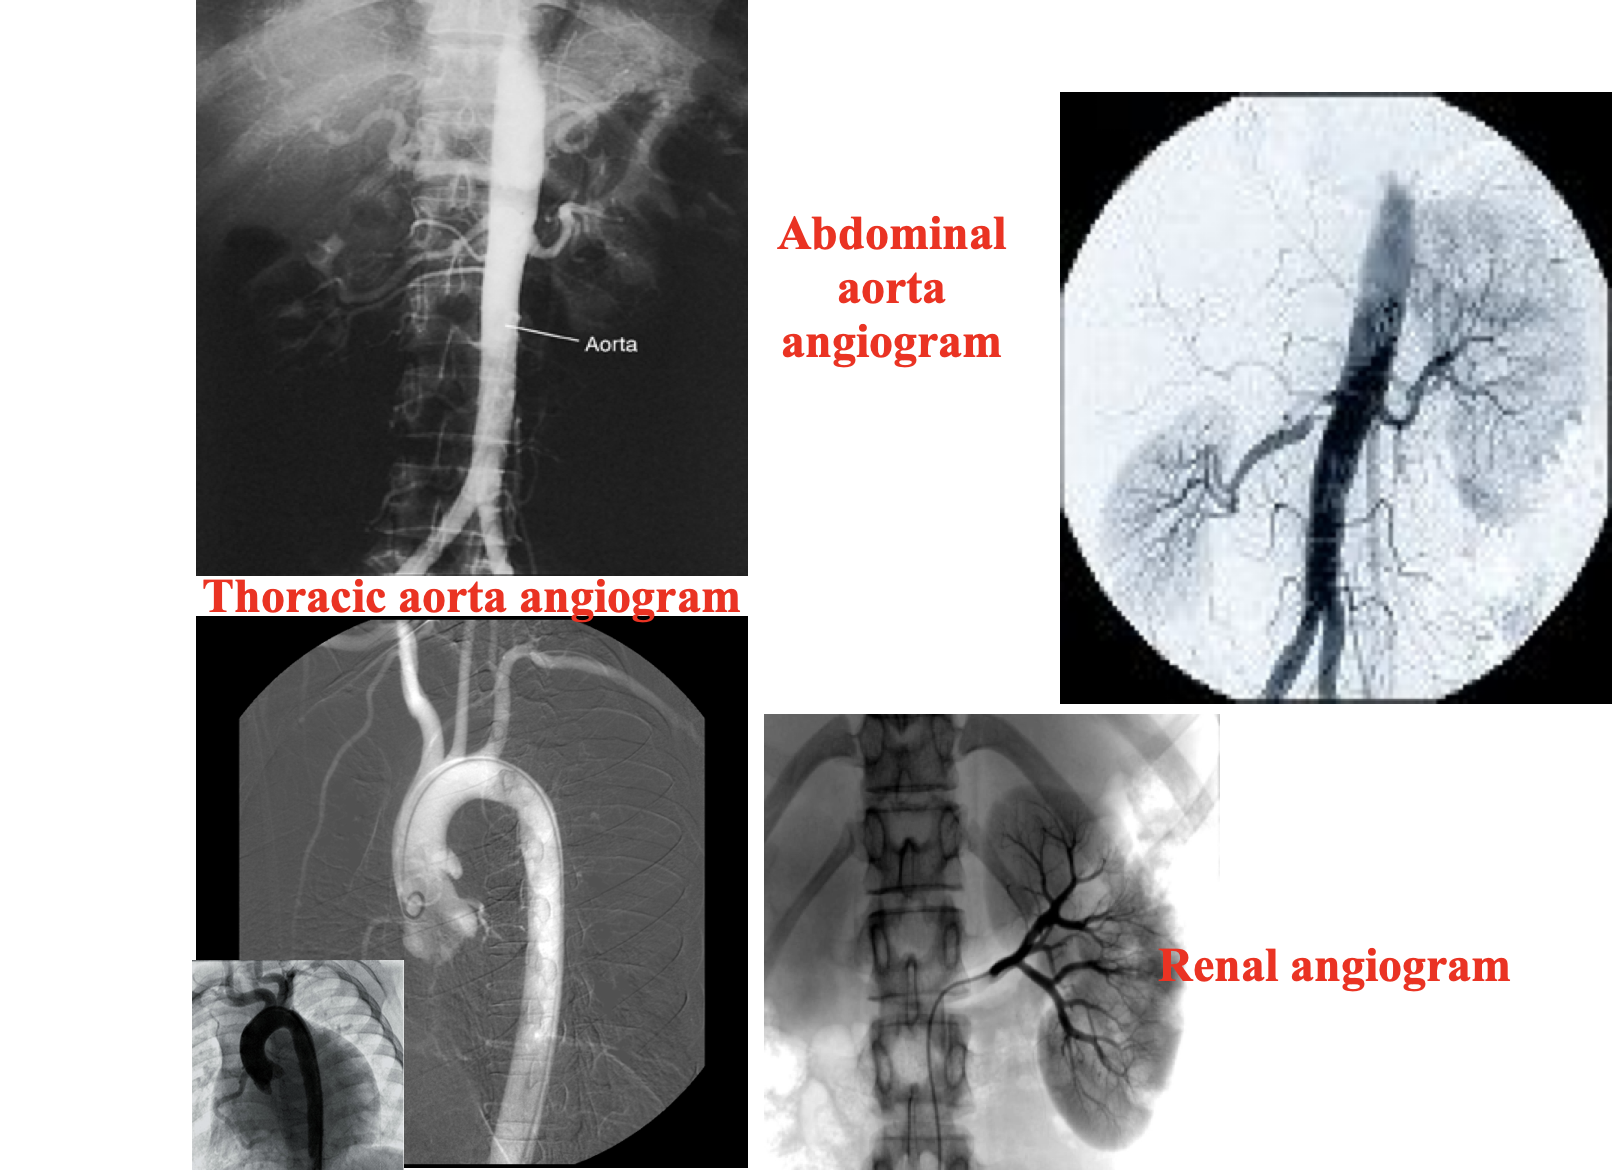

Conventional angiography

Radiographic visualization of blood vessels after injection of radiopaque contrast media into the blood vessels.Contrast is rapidly injected in to the blood vessel and a series of images are taken rapidly to follow the flow of contrast in the blood vessel. It is performed under fluoroscopy.

Angiography is indicated to diagnose vascular pathology. Conventional angiography is diagnostic as well as therapeutic.